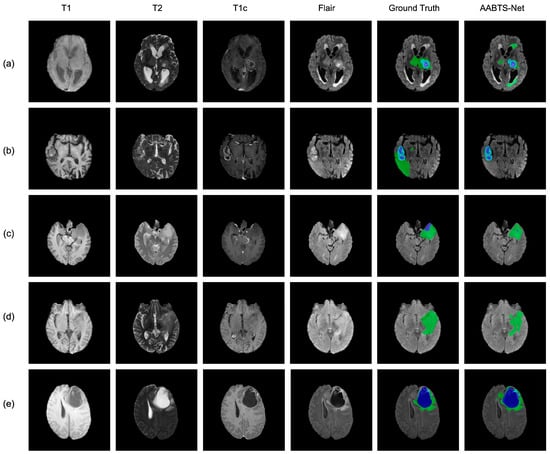

4.1.1. The Experiment Results on the BraTS 2019 Dataset

4.3. Analysis of the Bad Tumor Segmentation Results

| Cases | DSC | |||

|---|---|---|---|---|

| ET | TC | WT | AVG | |

| (a) BraTS2021_00493 | 0.885 | 0.924 | 0.270 | 0.693 |

| (b) BraTS2021_00494 | 0.964 | 0.990 | 0.730 | 0.895 |

| (c) BraTS2021_01666 | 0 | 0.738 | 0.916 | 0.551 |

| (d) BraTS2021_01179 | 1.000 | 0 | 0.769 | 0.590 |

| (e) BraTS2021_01293 | 0.541 | 0.929 | 0.874 | 0.781 |